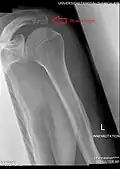

Plan of ossification of the scapula. Posterior side. Acromion visible at upper left, in blue. -

Radiograph of the shoulder showing an os acromiale